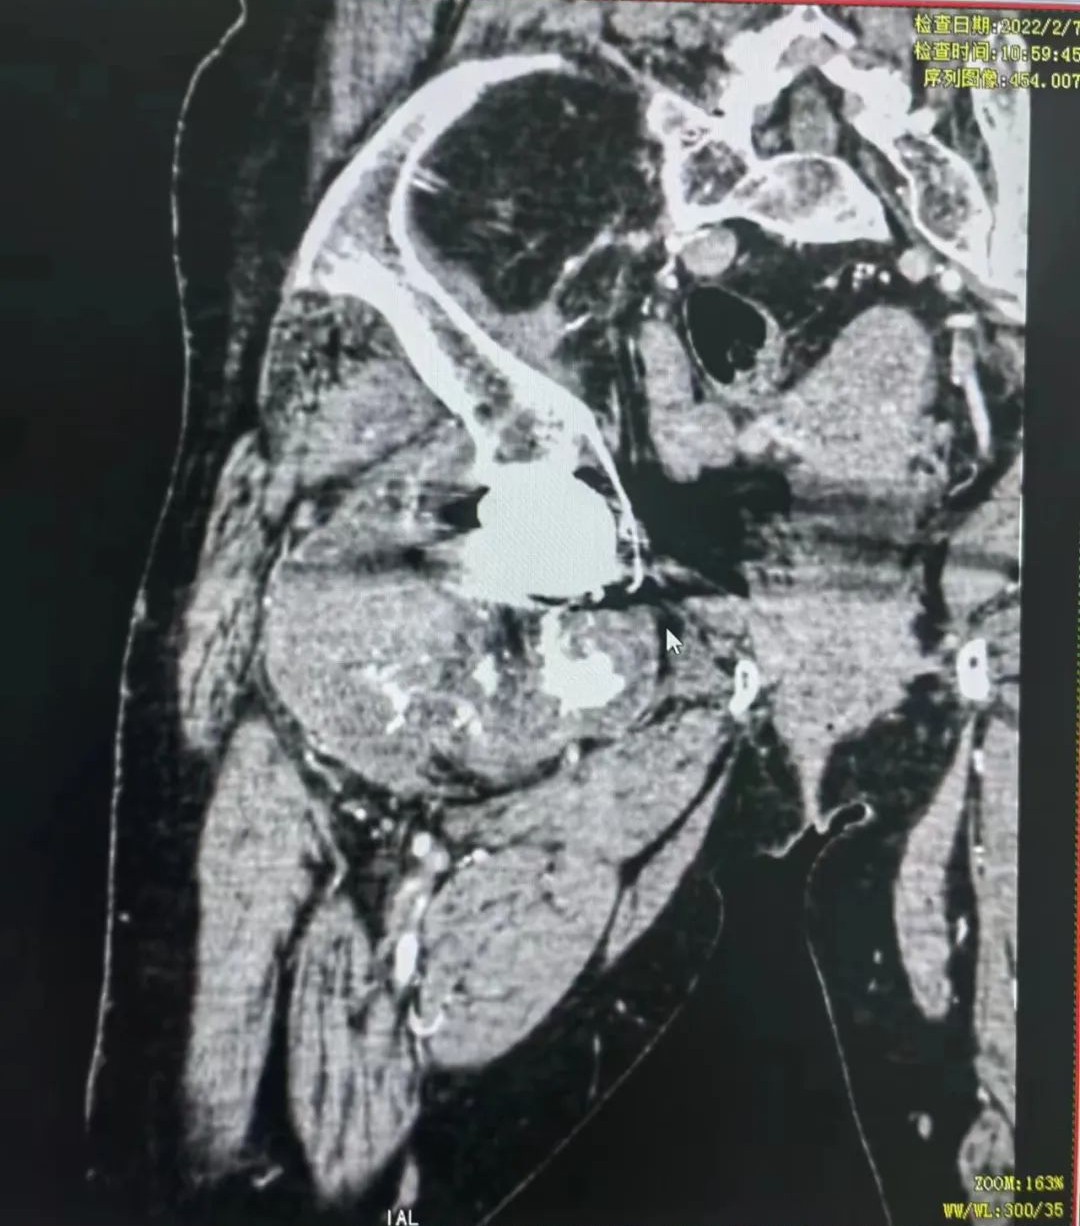

今年59岁的张阿姨,四年前就因为患上了良性肿瘤置换了右髋关节。2021年底,张阿姨右髋部又长出了一个大包块,按之有疼痛感,起初张阿姨并没有在意,后来越来越严重。到当地金瓶梅电影 检查发现,张阿姨是考虑恶性肿瘤(软骨肉瘤)复发,肿瘤从胯部的髋关节处一直延伸至大腿的股骨处,约为24厘米长,当地金瓶梅电影 建议到省城金瓶梅电影 看看。

张阿姨的肿瘤从胯部的髋关节处一直延伸至大腿的股骨处

辗转省城多家金瓶梅电影 ,都被告知要“截肢”,而且须截除半骨盆。原来,复发的肿瘤不仅破坏了股骨近段,包绕了原来的关节,而且造成同侧骨盆受累,为了最大程度将肿瘤切除干净,手术就须切除半骨盆及同侧髋关节。如果保肢,就要在原本难度颇高的髋关节复发病灶扩大切除术的基础上进行半骨盆置换,手术难度和危险系统都呈几何倍数增加,对于金瓶梅电影 和医生来讲都是个很大的挑战。